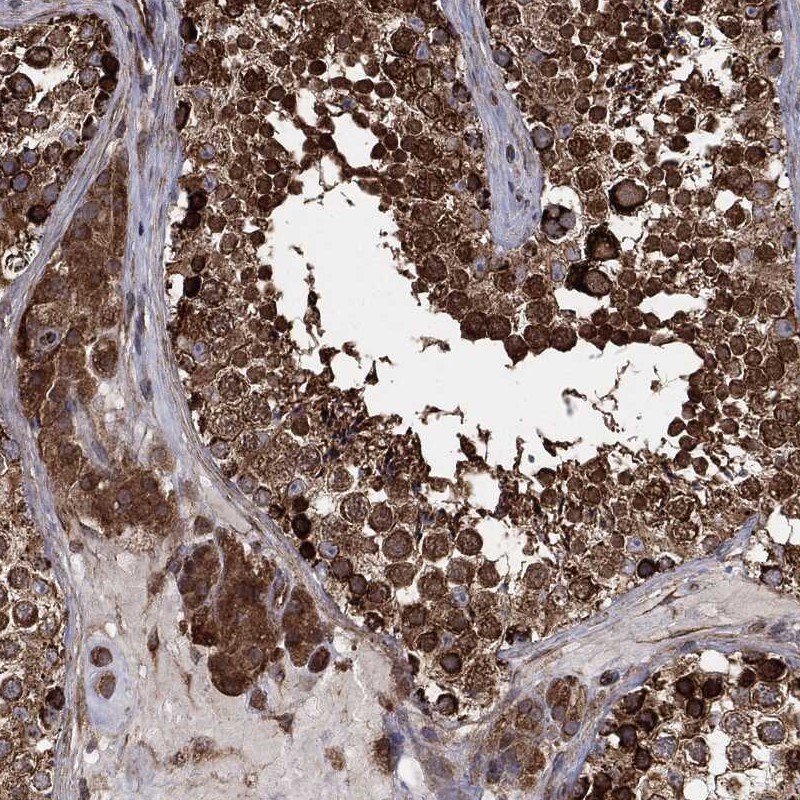

Immunohistochemical staining of human testis shows strong cytoplasmic positivity in cells in seminiferous ducts and Leydig cells.